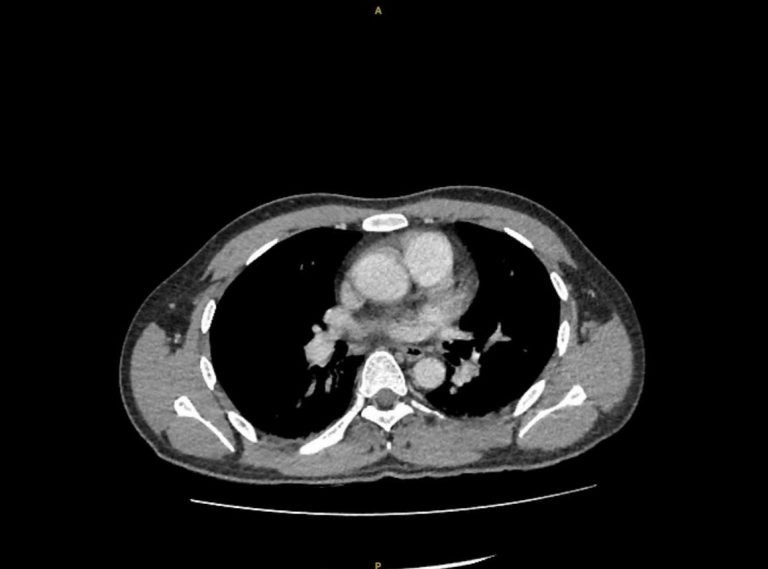

Hình ảnh cận lâm sàng sau khi đặt Sonde JJ dẫn lưu - Ảnh BVCC

Ê-kíp các bác sĩ khoa Ngoại tiết niệu, Bệnh viện Đa khoa Xuyên Á và các bác sĩ cấp cứu đã nhanh chóng vừa hồi sức vừa chỉ định đặt thông JJ cấp cứu từ bể thận trái xuống niệu quản và bàng quang. Thủ thuật này nhằm giải phóng chỗ tắc nghẽn do sỏi, giúp nước tiểu và mủ trong thận được dẫn lưu ra ngoài, giảm áp lực và kiểm soát ổ nhiễm trùng.

Trong quá trình can thiệp, ê–kíp ghi nhận mủ chảy nhiều từ thận xuống bàng quang. Mủ được cấy để phân lập vi khuẩn giúp điều trị kháng sinh theo đúng loại vi khuẩn gây bệnh. Trong lúc chờ đợi kết quả các bác sĩ cũng sử dụng kháng sinh theo phác đồ điều trị nhiễm khuẩn nặng.